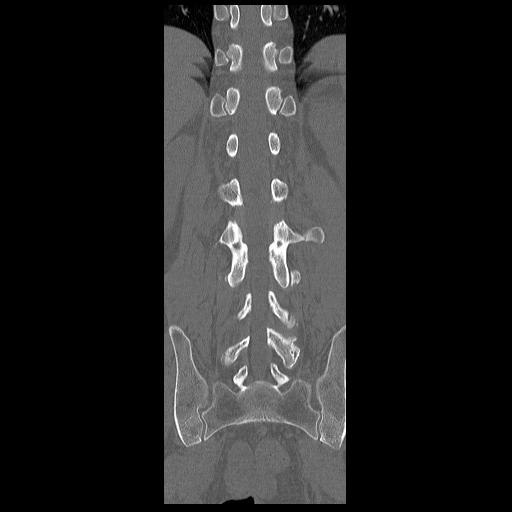

CT의 RECON영상입니다.

자세히 보시면 아시겠지만 좌측 3번 횡돌기도 부러졌지요. 1,2,3번 모두 부러졌습니다.